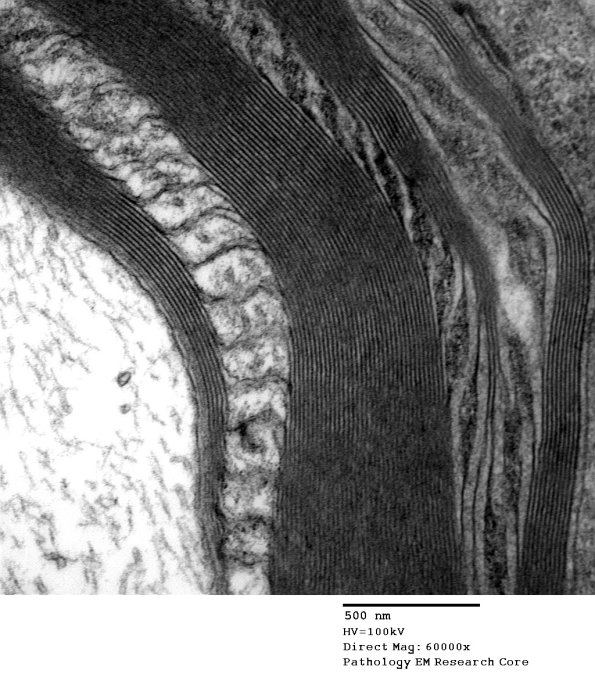

Higher magnification of image #4A4. (electron micrograph)